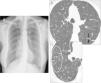

(A) Posteroanterior chest radiograph where diffuse bilateral micronodular interstitial pattern can be observed. (B) Thoracic HRCT image showing “tree-in-bud” pattern, consisting of branching structures (black arrows) and buds (white arrows). (C) A wider view with abundant peripheral buds (circle, C).

We present the case of a 56-year-old Caucasian woman who has never been a smoker and has no notable family, work, or pharmacological history. For the past 2 years, she has experienced daily persistent productive cough and dyspnea upon moderate exertion. Physical examination revealed bibasilar dry rales. The basic analytical data were normal, except for rheumatoid factor 53IU/ml (normal <20IU/ml) and immunoglobulin A 484mg/dl (normal 82–453mg/dl). Chest radiograph (Rx) showed small bilateral nodular opacities and thoracic high-resolution computed tomography (HRCT) demonstrated “tree-in-bud” pattern (Fig. 1). Spirometry revealed a mild restrictive pattern and the 6-min walk test showed a drop in arterial oxygen saturation from 98% to 90%. Echocardiogram was normal. Bronchioloalveolar lavage showed 87% neutrophils, CD4/CD8 ratio 1.16, and transbronchial biopsy showed no alterations. Given the lack of a definitive diagnosis, a surgical lung biopsy (SLB) was taken. The anatomopathologic study revealed chronic inflammation located mainly in the respiratory bronchioles, with lymphocytes, plasma cells, and foamy histiocytes; in the bronchiolar lumen, neutrophils were predominant. All these histologic data fit the diagnosis for DPB. Treatment was initiated with oral clarithromycin (250mg every 12h) and during the first 6 months of follow-up, the patient has presented good tolerance of the treatment prescribed, although the initial symptoms persist.